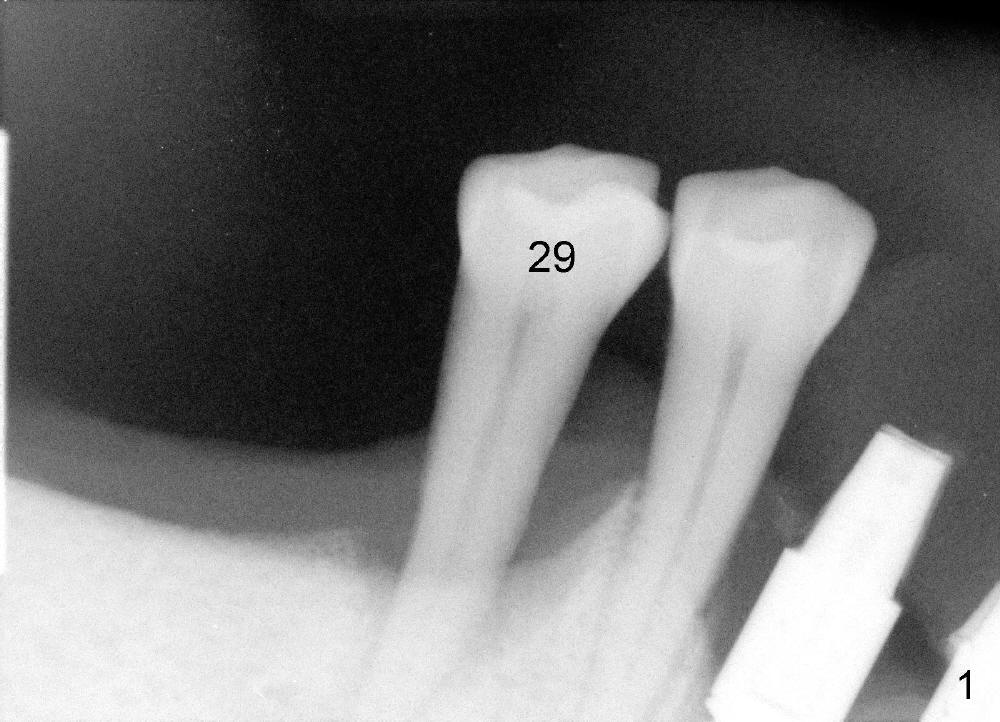

To avoid paresthesia on the right side, several preop PAs are taken (Fig.1-4) so that we know how to take good X-ray for this gagging patient. At first, #2 Sensor is used to take the first PA (Fig.1). It does not show the apex of the tooth #29. The second PA is a little better (Fig.2), but the mental nerve is out of view. Then #1 sensor is used. It allows us to position the sensor lower (Fig.3), but the image is blurred. When it is retaken, the image is clear (Fig.4), showing the proximity of the mental nerve loop (Fig.4': red dashed line) to the root tip of the tooth #29 (R).